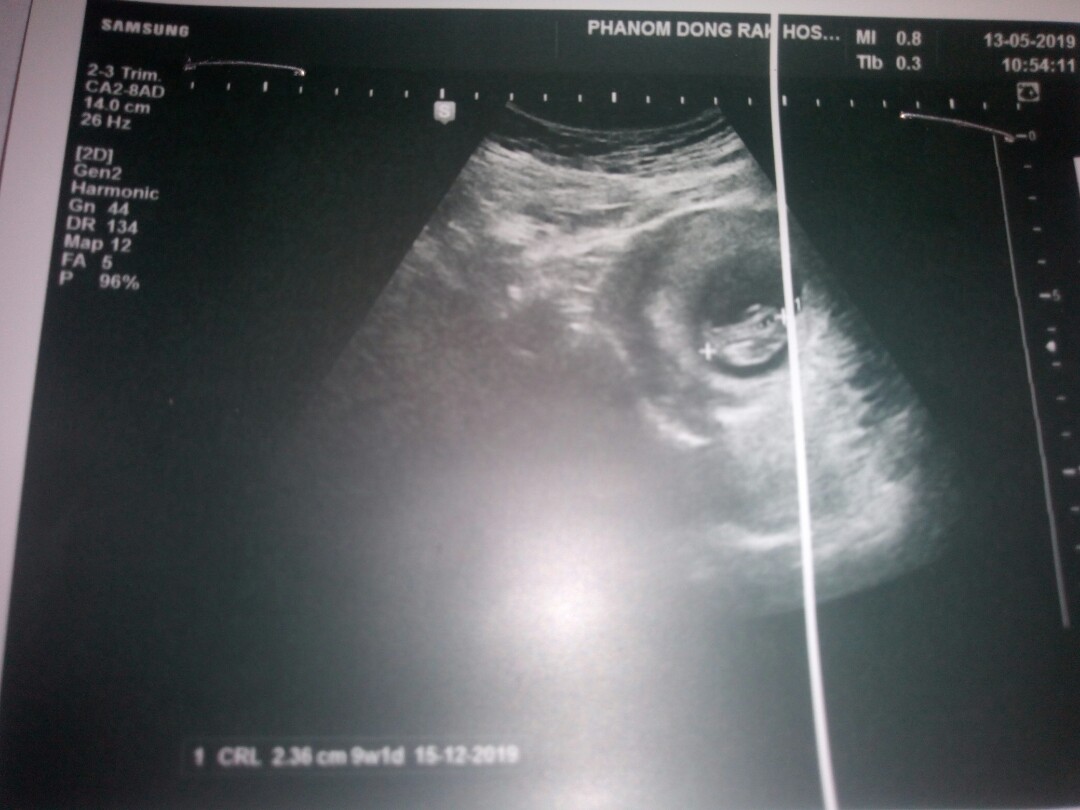

9wค่ะ